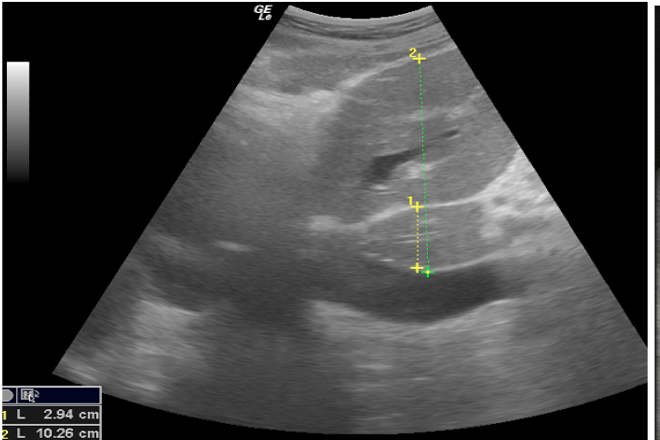

El hígado  normal  presenta  una  ecoestructura  homogénea   similar  a la  del  bazo  y  mayor  que  la  corteza  del  riñón ,  en su  interior  se  observan  pequeñas  áreas  anecoicas  redondeadas  o  lineales  correspondientes  a  venas   las  cuales  corresponden al  sistema  porta ,  las  cuales   a la  exploración  ecográfica  presentan  una  pared  ecogénica .

También  se  debe  realizar  la  exploración  en  cortes  longitudinales,  y  se   reportará:

Hígado: forma  y  tamaño  normales, limites  bien definidos, parénquima  homogéneo  sin  evidencia  de lesiones, ecogenicidad  normal  imagen  de  vasos  sin  anormalidades , vías  biliares  intrahepáticas   sin anormalidades.